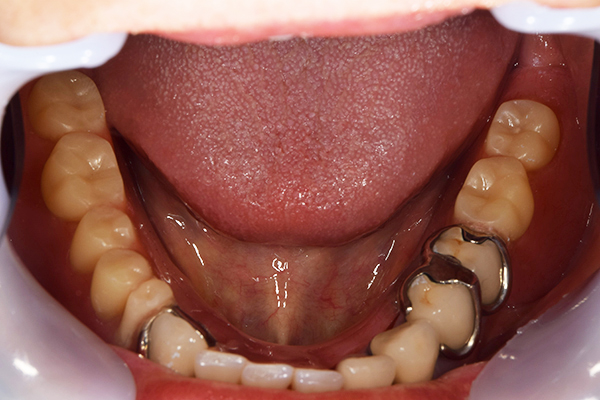

ケース2(自費の総入れ歯と部分入れ歯)

上下の入れ歯が外れやすくなったということでいらっしゃいました。 顎の骨はしっかりしていましたので、精密な型取りさえすればしっかりした入れ歯がつくれると思いました。 また下には6本歯が残っていましたが、虫歯になっている歯もありました。 かぶせ物のなかで大きな虫歯があった歯があり、1本だけ残せない状態でした。

上の入れ歯は確かに吸着は甘くなっていました。 また下の入れ歯はバネの一部が壊れており、安定感がなくなっていました。

精密な型取りの後、噛み合わせのチェックをしていきました。 かぶせ物も同時に作っていきました。

歯を並べた後、かぶせ物のフレーム作ってもらいました。先に歯を並べて理想の位置を決めておくことが大切です。

完成した入れ歯とかぶせ物です。 入れ歯への寛容度が高い患者様でしたので、 金属は使用せず、プラスチックのみで上は仕上げました。 下顎も歯は1本減ってしまいましたが、しっかり 入れ歯が維持できる様な構造にしました。

お口の中に入れた状態です。 見た目も最初とほとんど変わることなく作成できました。 維持や吸着に関しても問題ないようでした。

年齢 80歳・女性

主訴 上下の入れ歯が外れやすくなった

治療期間 3ヶ月

治療費 .メタルボンドクラウン:550,000円

.義歯:990,000円(税込、上下)

治療方針 長年使ってきた義歯の人工歯が磨耗し、臼歯部での咬合がすくなくなり、入れ歯の安定も悪くなり、あたりどころが悪くなって痛みが出ている。 そのため、入れ歯を上下作りかえる必要がある。

治療内容 過去に治療を行ったことのある歯が再度虫歯になってしまっているところがあり、すでに残せない状態にまでなっていたため、歯を一本抜歯した。 その後、かぶせ物と入れ歯を同時に作成していった。

特記事項 歯を抜いた後は、2〜3ヶ月歯ぐきの回復を待ってから入れ歯を作るため、待機期間があります。その間、古い入れ歯を調整しながらそのまま使うか、新し物をつくっておく必要があります。ただし、入れ歯は保険治療で作成する場合、6ヶ月は新しいものが作れないという決まりがあるので保険で全て作りたい場合は注意が必要です。